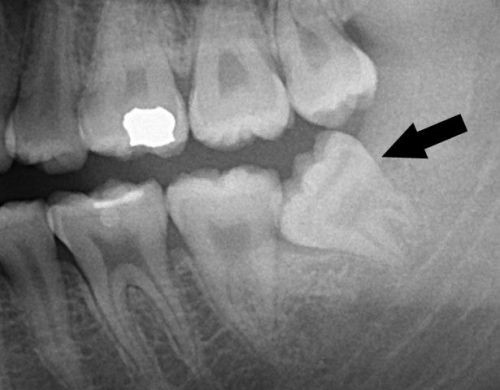

Từ đó dẫn đến những tình trạng mọc sai vị trí của răng khôn như là: mọc lệch, mọc chồng lên răng khác, răng mọc chen chúc nhau, răng mọc ngầm, răng mọc ngang, răng mọc ngược vào xương hàm…gây ra những cơn đau, khó chịu kéo dài, sưng tấy, đỏ viêm ở vùng lợi răng mọc.

Có những người không quan sát được răng khôn mọc lên nhưng thực tế có thể vẫn có răng khôn mọc lệch hoặc mọc ngầm ở dưới xương hàm và bị mô mềm che phủ. Răng số 8 bị mọc lệch gây ra rất nhiều biến chứng ảnh hưởng đến sức khỏe răng miệng và sức khỏe toàn diện của cơ thể người bệnh.

Răng số 8 mọc lệch thường làm hỏng răng bên cạnh là răng số 7. Tình trạng mọc lệch hình thành nên khe hở giữa răng khôn và răng số 7 dễ làm kẹt lại thức ăn, khiến khó vệ sinh, lâu ngày chắc chắn gây ra sâu răng. Khi răng khôn mọc lệch làm ép vào răng bên cạnh làm tiêu biến mất một phần thân và chân răng này.

Quá trình tổn thương có thể diễn ra trong âm thầm kéo dài trong nhiều năm, và cho đến khi bạn phát hiện ra thì tổn thương đã lan rộng gây biến chứng nặng. Khi đi đến phòng khám kiểm tra thì đôi khi răng số 7 đã bị hỏng, hư hại nặng không thể giữ lại được.